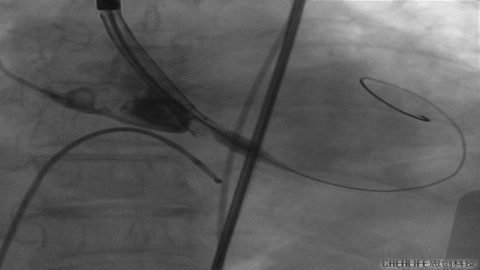

发生瓣叶切割,无窦侧瓣叶切割,Type0结构形变为类三叶瓣结构。

更换VenusA26号瓣膜前1/3

VenusA26号完全释放